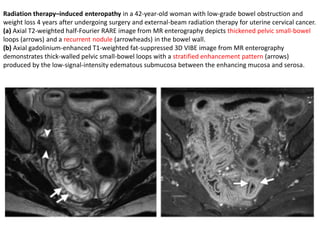

thin, slightly enhancing

walls containing smooth

muscle.

• These structures are